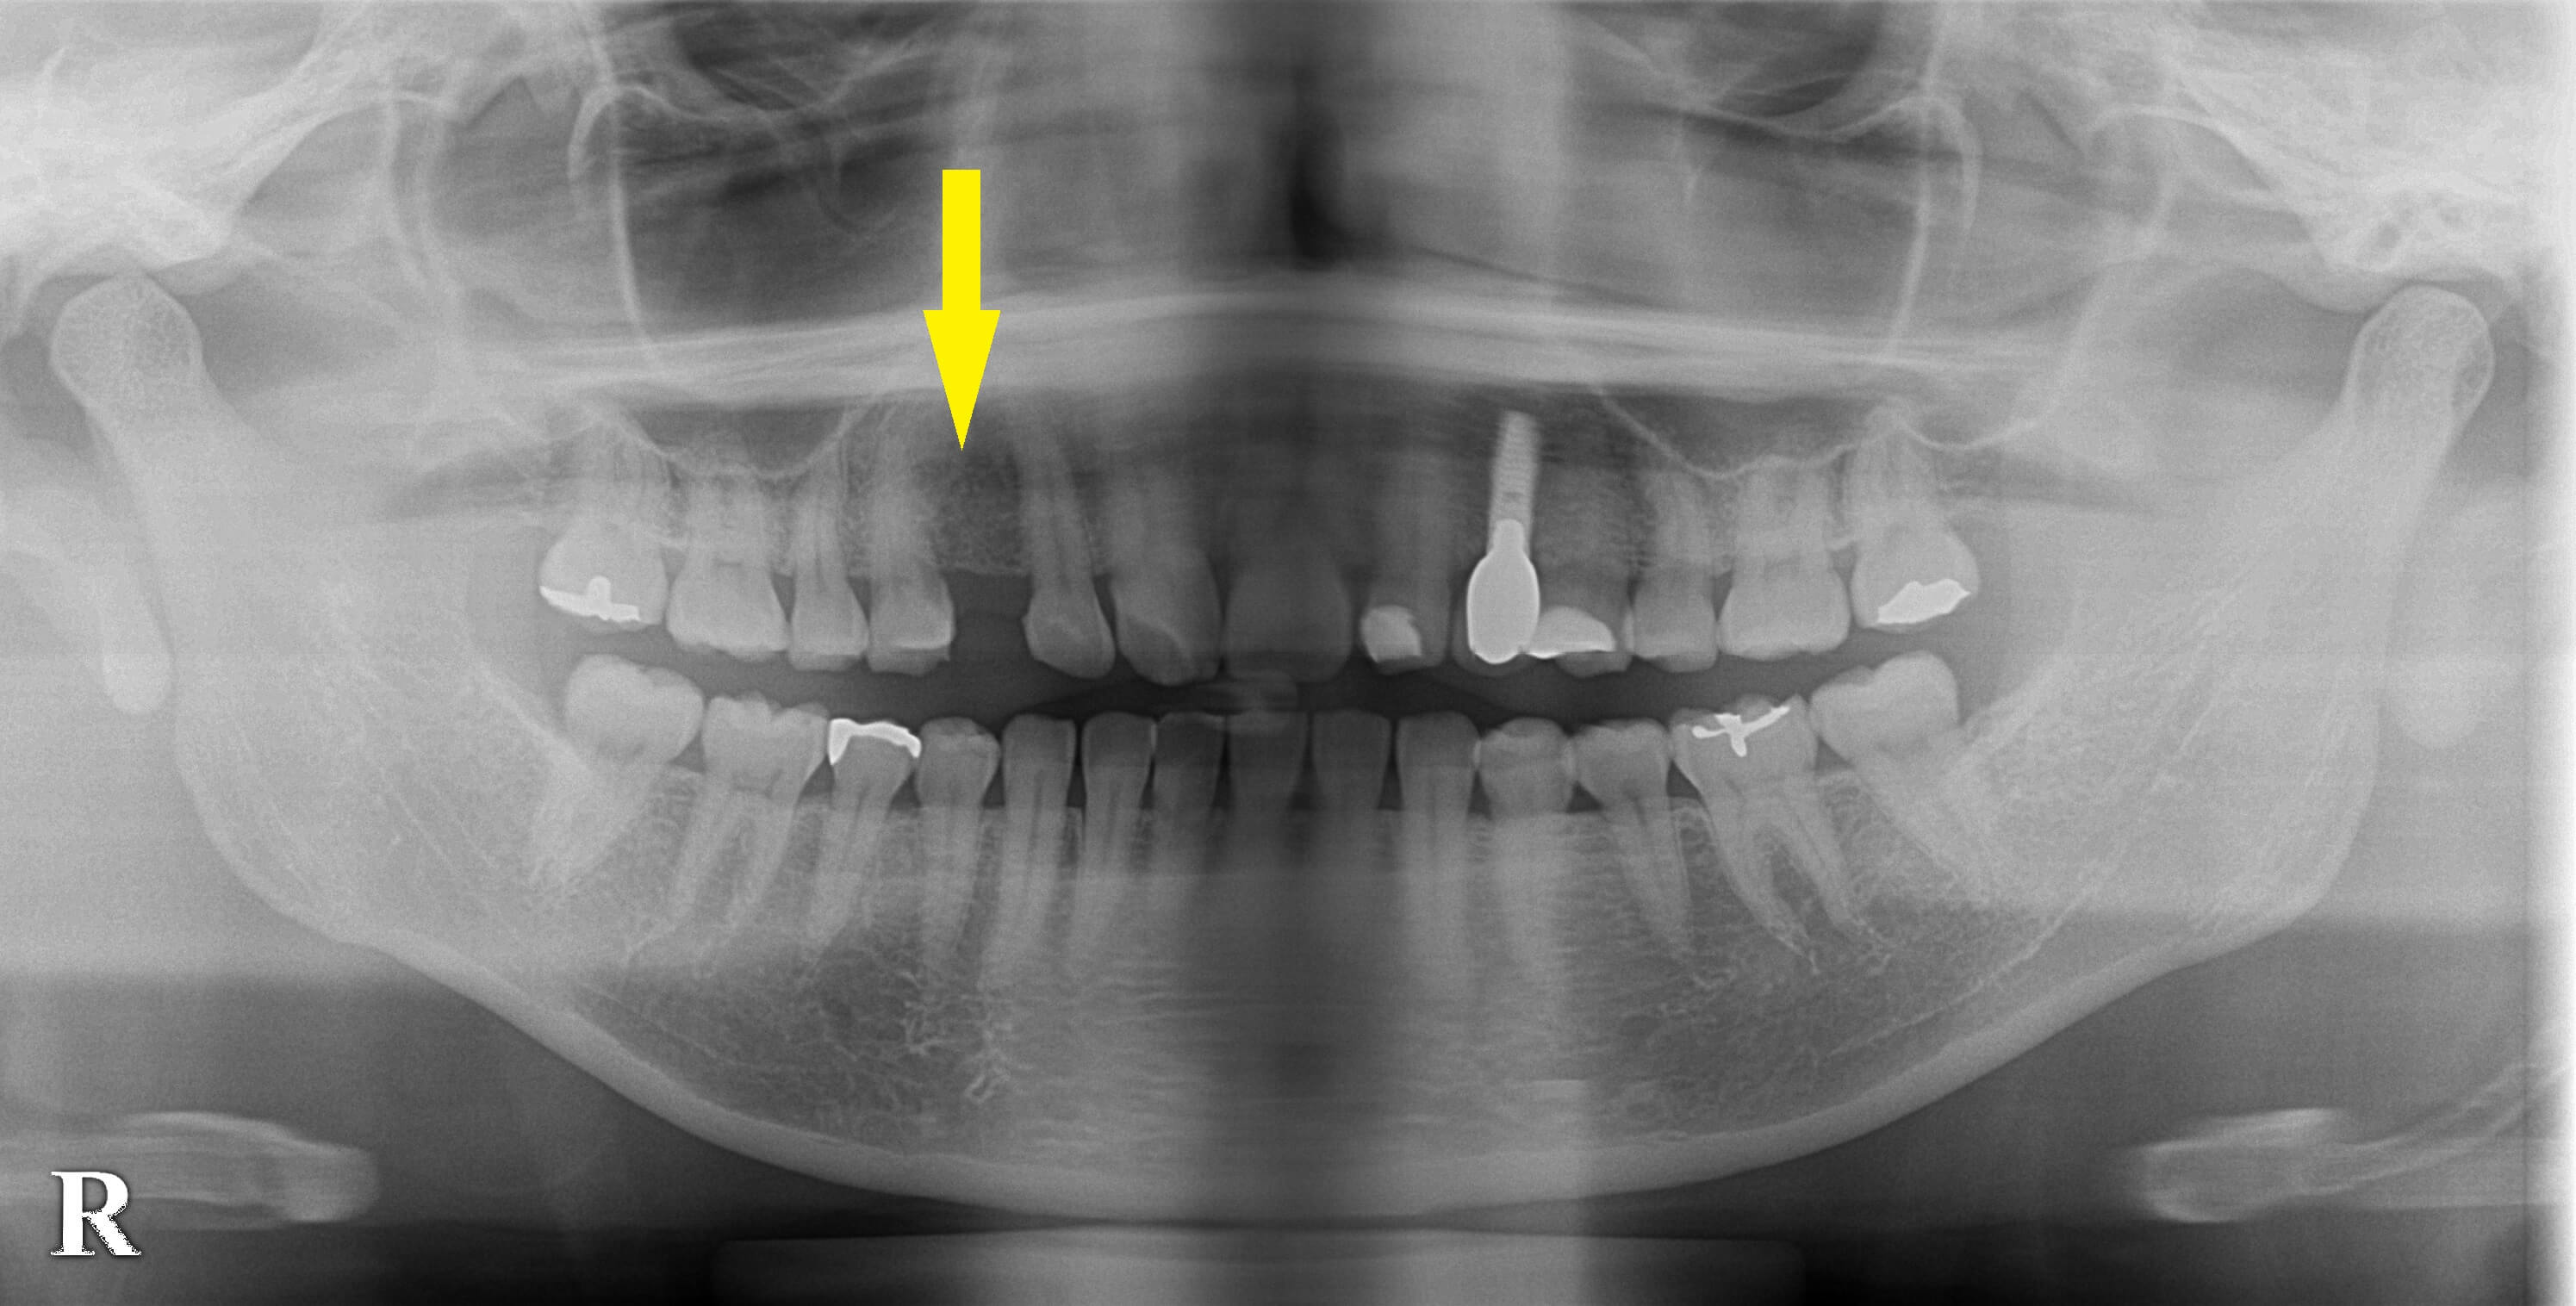

永久歯の欠損はインプラントで 今週のインプラント症例 2021.08.122026.01.19 患者様は名古屋在住の30代女性。 上顎の永久歯の犬歯が、左右とも先天性欠損で、乳歯が抜けてしまったままになっていました。 左側は数年前にインプラント治療をされており、今回は右側の犬歯のインプラント治療を希望されて来院されました。 レントゲン、CTにて、骨はやや薄めでしたが、骨造成を必要とするほどではなかったため、通常の埋入手術で十分と判断しました。 本日、同部1本のインプラント埋入術を行いました。 症例・コラム一覧に戻る